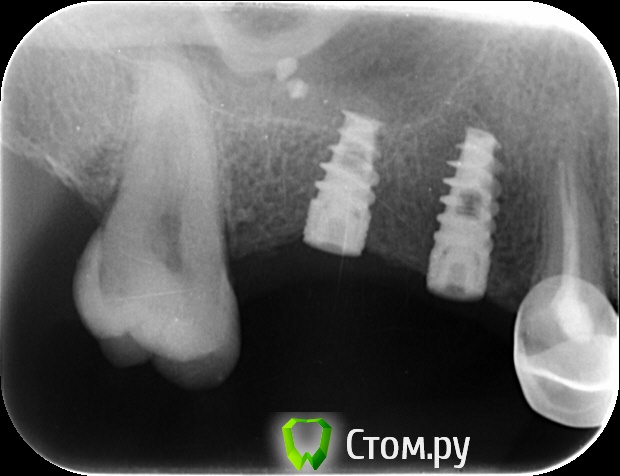

an_ver Опубликовано 15 сентября, 2014 Автор Поделиться Опубликовано 15 сентября, 2014 Вот такая картина на сегодня Ссылка на комментарий

zzkz Опубликовано 15 сентября, 2014 Поделиться Опубликовано 15 сентября, 2014 Бикортикально ставили 2.6? Ссылка на комментарий

an_ver Опубликовано 15 сентября, 2014 Автор Поделиться Опубликовано 15 сентября, 2014 Бикортикально ставили 2.6?Ставил не я,в другом городе Ссылка на комментарий

Дмитрий Никитюк Опубликовано 15 сентября, 2014 Поделиться Опубликовано 15 сентября, 2014 Не смертельно. Тут даже после установки фдм ситуация улучшится. Резорбция не страшна, пока поверхность имплантата не инфицирована. Считайте, что у Вас уже произошло ремоделирование. Подсадка ССТ спасёт ситуацию. 4 Ссылка на комментарий

Aquarius Опубликовано 15 сентября, 2014 Поделиться Опубликовано 15 сентября, 2014 Полностью согласен, ставьте ФДМы и все. Если заморочиться, то можно и ССТ . А так Дмитрий прав, все самое страшное ( ремоделировка))) по сути уже позади Ссылка на комментарий